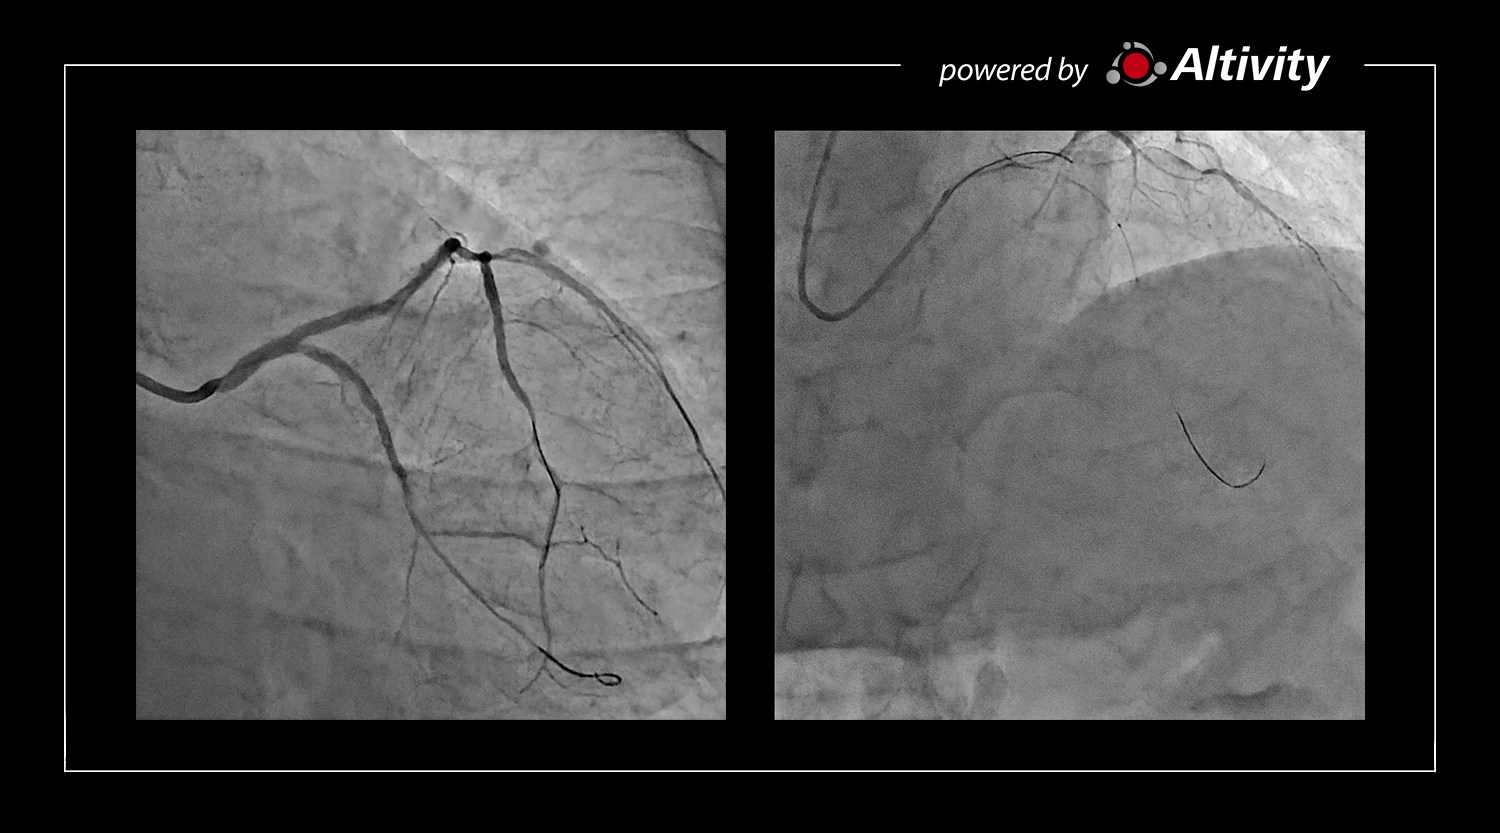

Дивіться чіткіше з αEvolve Imaging у режимі реального часу

Чітке флюороскопічне зображення підвищує впевненість і може допомогти покращити клінічні результати, ефективність процедур і зменшити частоту цифрового отримання даних, що призводить до подальшого зниження дози для пацієнтів і операторів.

Завдяки шумозаглушенню на основі глибокого навчання та багаточастотній обробці αEvolve може забезпечити вдвічі вищий коефіцієнт контрастності та шуму порівняно зі звичайною обробкою зображень.